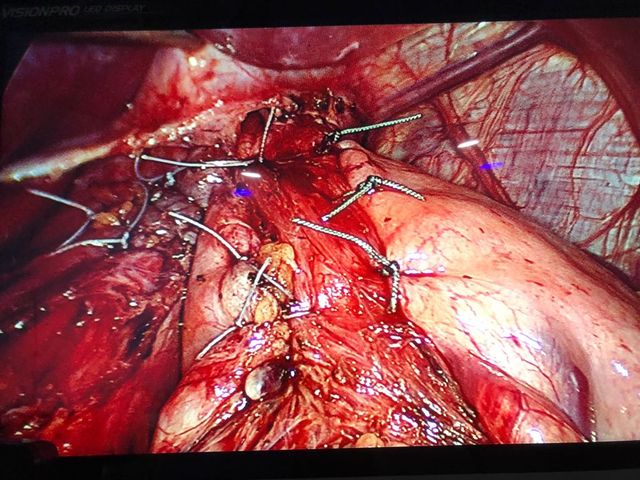

ALLPS hepatectomy 45 year old child’s A cirrhosis with normal LFT and no portal hypertension.

Interesting images October: ALLPS hepatectomy 45 year old child’s A cirrhosis with normal LFT and no portal hypertension. Planned for a right hepatectomy however intraoperative portal vein pressure was 13 mm ( preferably less than 8 mm) so altered strategy and did ALLPS (Associating Liver Partition and Portal vein Ligation for Staged hepatectomy) In ALLPS stage 1 we ligate portal vein, transect parenchyma fully by hanging and mobilise the right lobe fully. (Image 1,2 and 3) 7 to 10 days (8th day in our Pt)later depending on LFT trend we document the hypertrophy on CT scan and do the completion hepatectomy (pics . Although it has its own shortcomings in selected patients (like in our case ) it has been proven to achieve better degree of hypertrophy compared to Portal vein embolisation / portal vein ligation. Ideally useful for trisectionectomies.